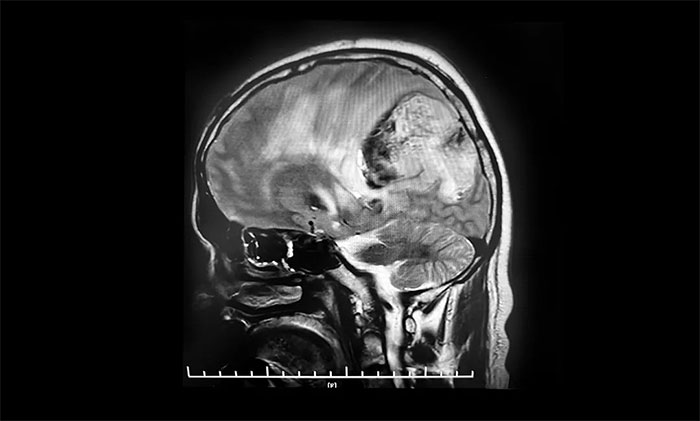

患者为45岁中年男性,在2009年4月体检时发现颅内占位性病变,就诊上海某三甲医院行头颅MRI增强提示,颅内有一8x8cm占位性病变,考虑肿瘤巨大并且位置深在,给予化学药物治疗。2021年,求医郑州某医院,给予中药治疗。2022年在当地三甲医院复查头颅MRI提示占位性病变,继续给予化学药物治疗。

今年10月7日,患者突发意识不清,伴右手不自主抖动,呼唤有反应,反应迟钝,立即就诊于当地医院。行头颅增强MR提示:左侧额顶叶、胼胝体体部及压部、丘脑占位伴左侧顶叶占位,范围较前明显增大,均以弥漫性胶质瘤考虑伴左顶叶肿瘤卒中出血。10月11日,患者症状较前加重,出现嗜睡,反应迟钝,右侧肢体肌力明显下降。当地医院表示无法救治,希望渺茫。

头颅MRI平扫+增强+DWI+MRA提示,左侧顶枕叶巨大肿瘤伴局部瘤卒中,幕上脑室系统、脑干受压变形,中线结构右移19mm,大脑镰下疝形成。李士其教授等专家团队会诊指出,患者脑内巨大占位,性质不明,并且患者已经发生脑疝昏迷,生命危在旦夕,应尽快进行手术治疗,挽救患者生命,同时明确病理诊断。